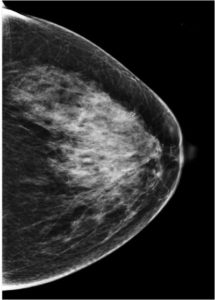

59 Yr old female, referred from outside for suspicious microcalcifications in left breast.